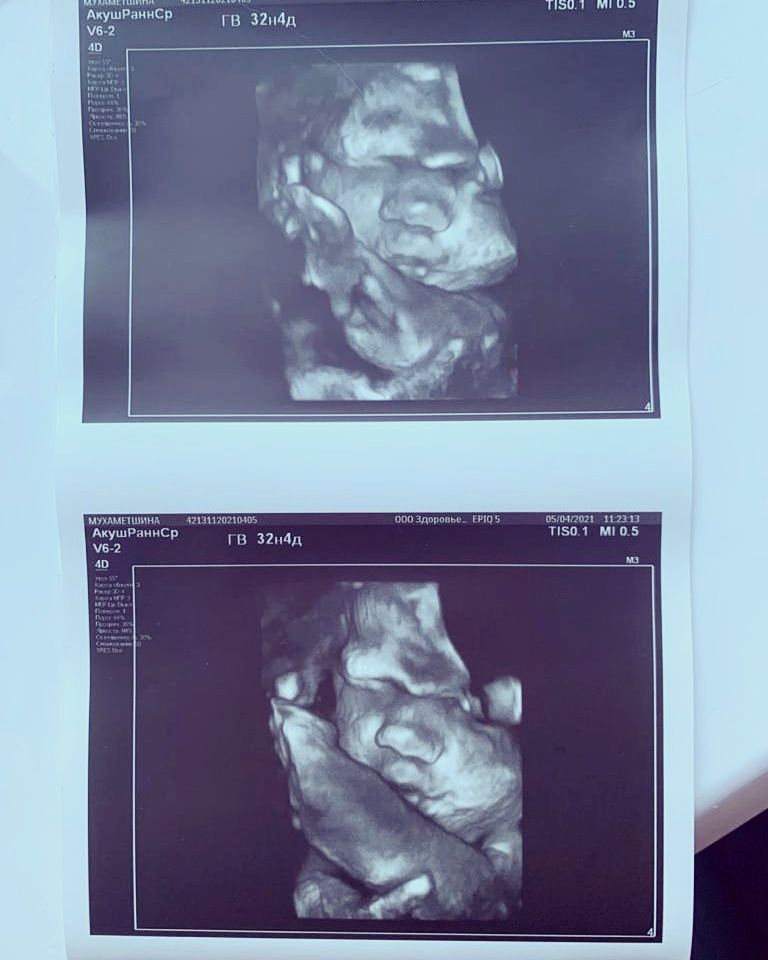

Прошли мы сегодня 3 скрининг, всё хорошо, небольшие мы, в принципе не в кого, тьфу тьфу тьфу, единственное что выделяется это папин носище, ну прям один в один 🤣